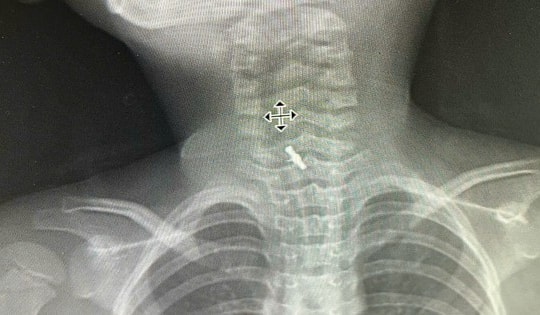

Bé gái 5 tuổi đau rát họng, bác sĩ gắp ra "thứ đáng sợ" bên trong

Bé gái 5 tuổi nhập viện vì đau rát họng, bác sĩ phát hiện thứ "quen thuộc" bên trong